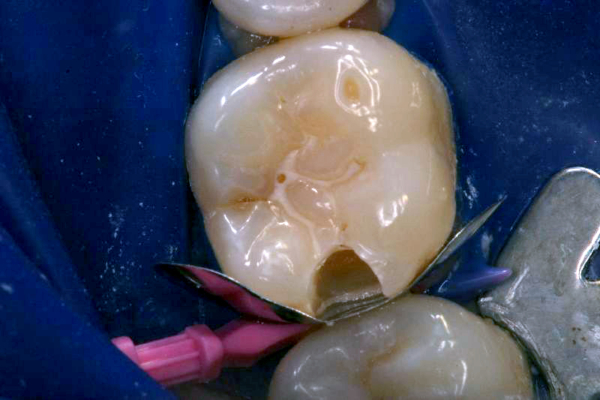

Click on an image below to enlarge & view caption.

Dentistry and photography courtesy of Dr. Robert Margeas.